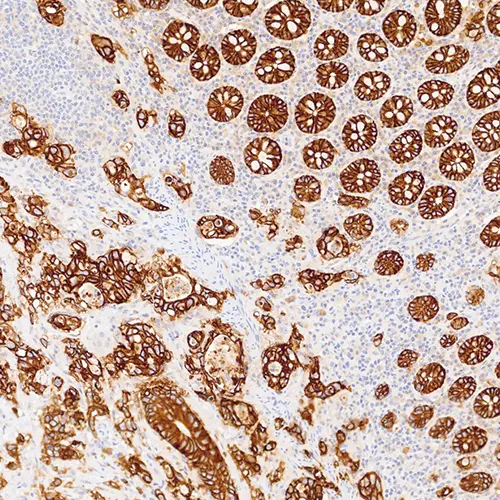

Bowel Adenocarcinoma: EpCAM clone EPR20532-222.

Epithelial Cell Adhesion Molecule (EpCAM) was one of the first tumor‐associated antigens identified and is a transmembrane glycoprotein expressed in most normal epithelial cells and overexpressed in a variety of carcinomas. It is involved in regulating normal cell-cell adhesion and may also have a role in the regulation of several oncogenes. It is not expressed in cancers of non‐epithelial origin, and therefore may be used as an aid for the differential diagnosis of several conditions.